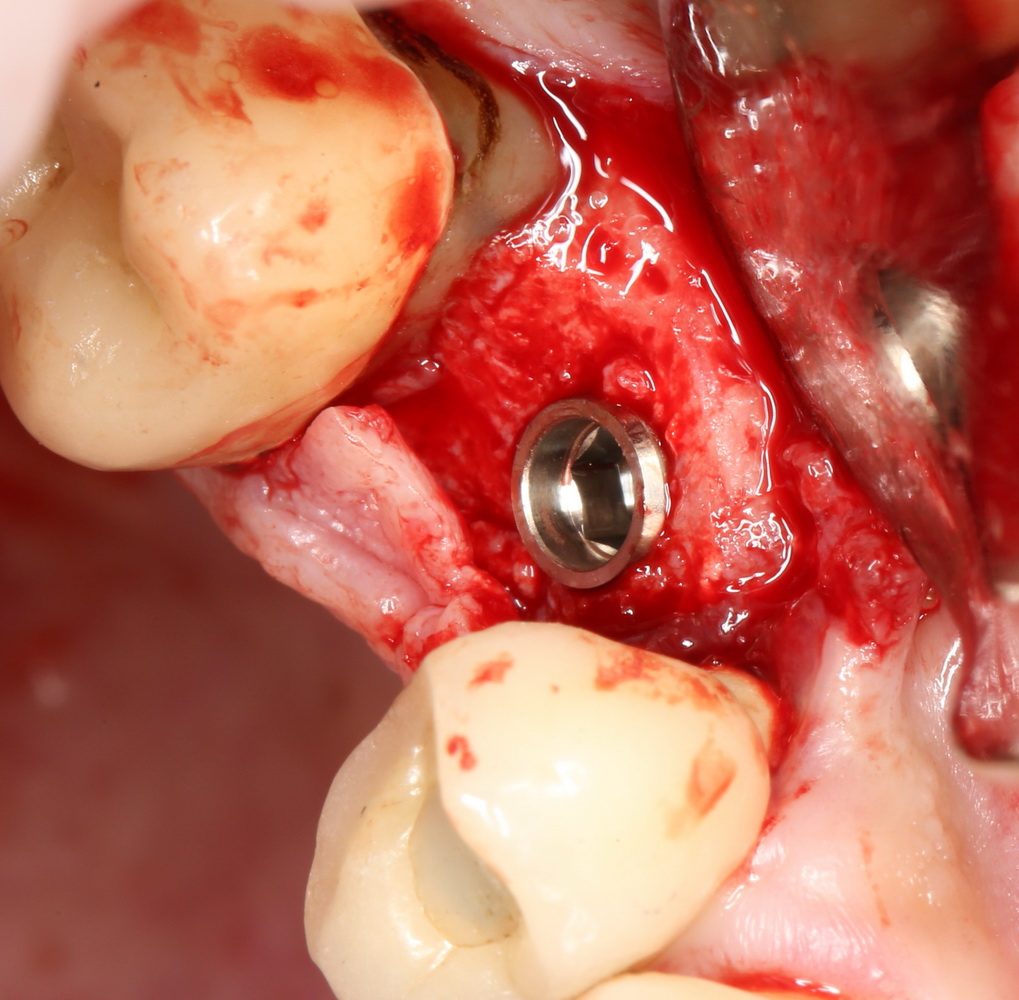

Начинаем с самого сложного — зуба #47:

Гранулема настолько большая, что ее видно из лунки:

Аккуратно ее удаляем. Приходится пожертвовать межкорневой перегородкой:

В лунку помещаем Neocones, Bioss Collagen:

Затем к краям лунки подшивается Mucograft Seal:

Ну и, сам имплантат. Разумеется Friadent XiVE:

Еще раз напомню, что все полированные части импланта любой системы должны находиться выше уровня костной ткани. Как на фотографии.